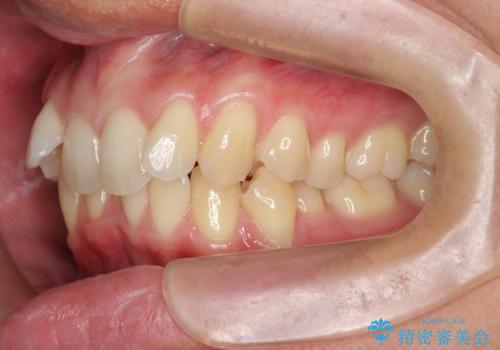

過蓋咬合・上顎前突・叢生を改善するマウスピース矯正

- 前歯のがたつき、不揃いさの改善を求めて来院されました。

・前歯の深い噛み合わせ (過蓋咬合)

・上顎前突(Angle Class2)

・叢生(がたつき)

20時間以上のマウスピース装着、ゴムかけを遵守していただいたおかげでしっかりと噛み合わせ、がたつきの改善を行うことができました。